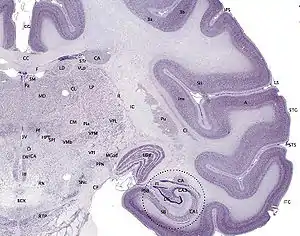

Cerebral cortex

The cerebral cortex is typically described as comprising three parts: the sensory, motor, and association areas. These sensory areas receive and process information from the senses. The senses of vision, audition, and touch are served by the primary visual cortex, the primary auditory cortex, and primary somatosensory cortex. The cerebellar cortex is the thin gray surface layer of the cerebellum, consisting of an outer molecular layer or stratum moleculare, a single layer of Purkinje cells (the ganglionic layer), and an inner granular layer or stratum granulosum. The cortex is the outer surface of the cerebrum and is composed of gray matter.[1]

The motor areas are located in both hemispheres of the cerebral cortex. Two areas of the cortex are commonly referred to as motor: the primary motor cortex, which executes voluntary movements; and the supplementary motor areas and premotor cortex, which select voluntary movements. In addition, motor functions have been attributed to the posterior parietal cortex, which guides voluntary movements; and the dorsolateral prefrontal cortex, which decides which voluntary movements to make according to higher-order instructions, rules, and self-generated thoughts.